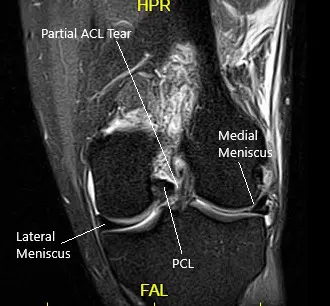

MRI suggested a complete rupture of the quadriceps tendon at the patellar attachment. The joint effusion communicates through the tendon defect with a prepatellar fluid collection. Low-grade intrasubstance tear at the origin of the ACL. Radial tear at the free edge of the lateral meniscal body.

MRI of the left knee in the sagittal and coronal view.